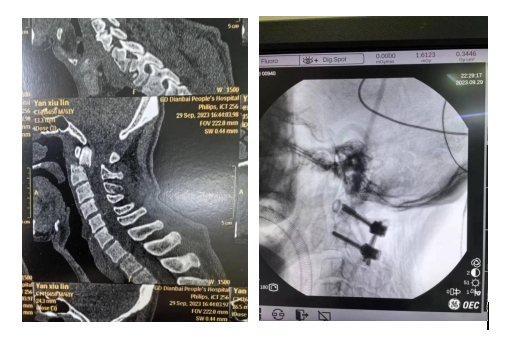

當(dāng)時(shí)嚴(yán)伯的傷情異常嚴(yán)重,接診醫(yī)生們都倒吸一口涼氣。急診醫(yī)學(xué)科立馬聯(lián)系骨科中心緊急會診,并完善相關(guān)檢查。CT結(jié)果提示:頸椎樞椎齒狀突骨折并寰椎后脫位。

據(jù)王清富介紹:上頸椎處于顱腦和頸椎的交界處,有重要的血管神經(jīng)環(huán)繞,手術(shù)風(fēng)險(xiǎn)高,技術(shù)要求復(fù)雜,一旦出現(xiàn)損傷往往出現(xiàn)嚴(yán)重后果,故上頸椎手術(shù)堪稱為脊柱外科的“皇冠手術(shù)”。

寰樞椎脫位是上頸椎最常見的嚴(yán)重?fù)p傷,分為可復(fù)位或難復(fù)性寰樞椎脫位。難復(fù)性寰樞椎脫位,作為一種重度畸形,不僅影響患者的美觀,而且會造成脊髓的受壓,甚至發(fā)生癱瘓可能,嚴(yán)重影響患者的生活質(zhì)量,同時(shí)給家庭帶來沉重負(fù)擔(dān)。對于難復(fù)性寰樞椎脫位所致畸形及脊髓受壓的治療更為棘手,如何將脊髓表面僵硬固定的脫位椎體復(fù)位,有效解除神經(jīng)壓迫,而不傷及脊髓,是手術(shù)的關(guān)鍵。

近年來我院骨科中心—脊柱外科團(tuán)隊(duì)在院領(lǐng)導(dǎo)的關(guān)心支持下,在王清富副院長的帶領(lǐng)下,成功開展頸后路椎弓根螺釘融合內(nèi)固定治療寰樞椎骨折脫位,為眾多患者解除了病痛,完成了一系列頸椎復(fù)雜手術(shù)的攻關(guān),是目前本地區(qū)率先開展此項(xiàng)技術(shù)的單位。